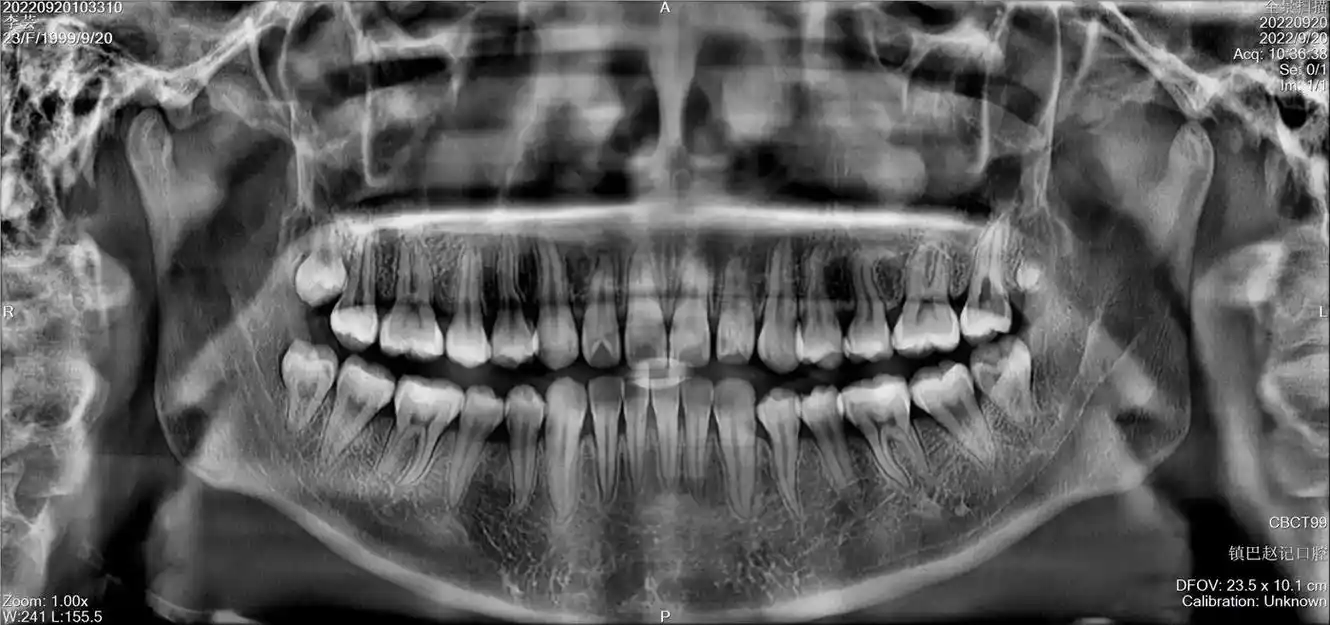

口腔全景片(曲面断层片)是口腔科检查中十分重要的常规检查手段,主要

口腔全景片提供的是二维影像,所以它的分辨率不如ct高,而且只能提供一